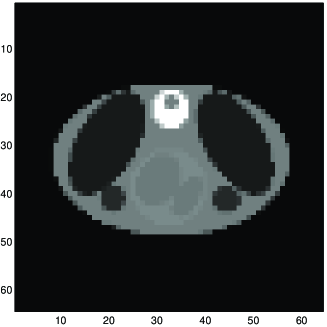

5.5. Inverse scattering and diffraction tomography

Fig. 9 shows an example of results in non linear diffraction tomography image reconstruction. In this figure a) is the original image, b) is the measured scattered field data, d) is a reconstruction using the linear Born approximation, and e) is a reconstruction using GNC.

|

|

|

| a | b | c |

a) original, b) linear Born approximation reconstruction, c) GNC based reconstruction